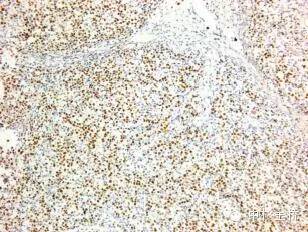

圖為EBER原位雜交染色DBA顯色,蘇木素復(fù)染

EBER是EB病毒編碼的小RNA,在EB病毒感染的細(xì)胞核中高拷貝存在。根據(jù)EBER的序列設(shè)計(jì)的EBER RNA探針,可以用于石蠟切片,具有較高的特異性和靈敏度,該試劑盒廣泛應(yīng)用于美國(guó)、歐盟等各國(guó)。

- RNA探針,定位準(zhǔn)確,敏感性強(qiáng)